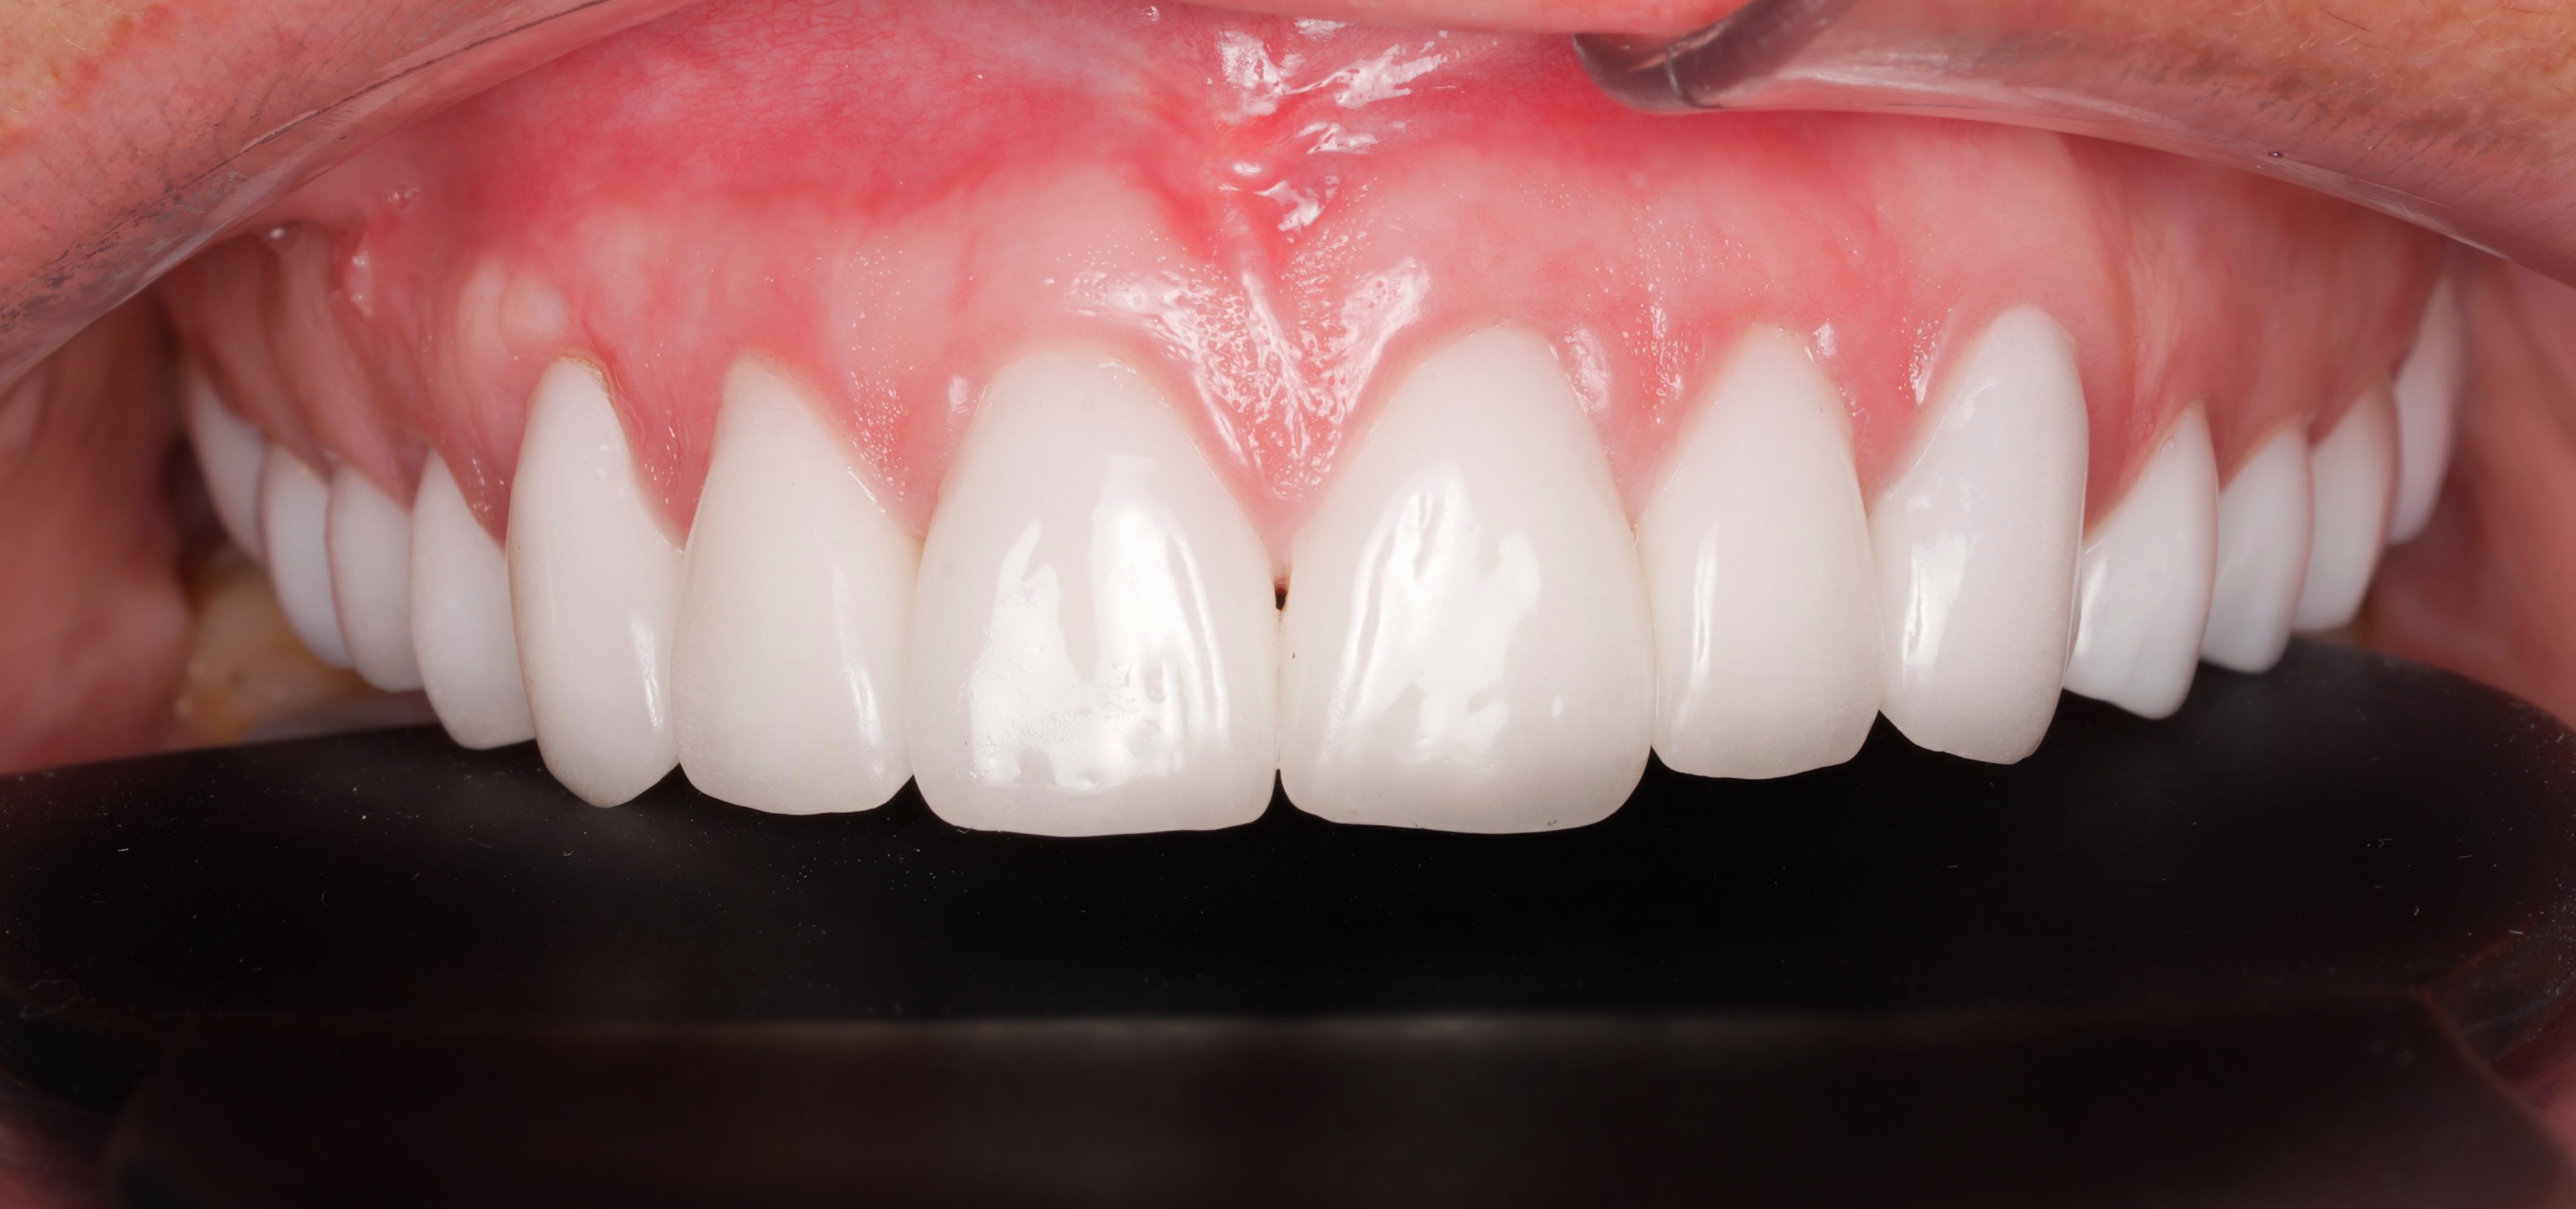

• Coronally Advanced Flap (CAF): The gum tissue is gently repositioned coronally (toward the tooth crown) to cover the exposed root.

• Connective Tissue Graft (CTG): Often used as an additional graft, it is harvested from beneath the patient’s palate and placed under the flap to increase tissue thickness and achieve complete root coverage.

• “Gold Standard”: The combination of CAF + CTG is considered the most effective method for achieving full root coverage, restoring a natural gum contour, and preventing further periodontal issues.

• Complete coverage of the exposed root and restoration of a harmonious gum line.

• Noticeable improvement in smile aesthetics, especially in the anterior region.